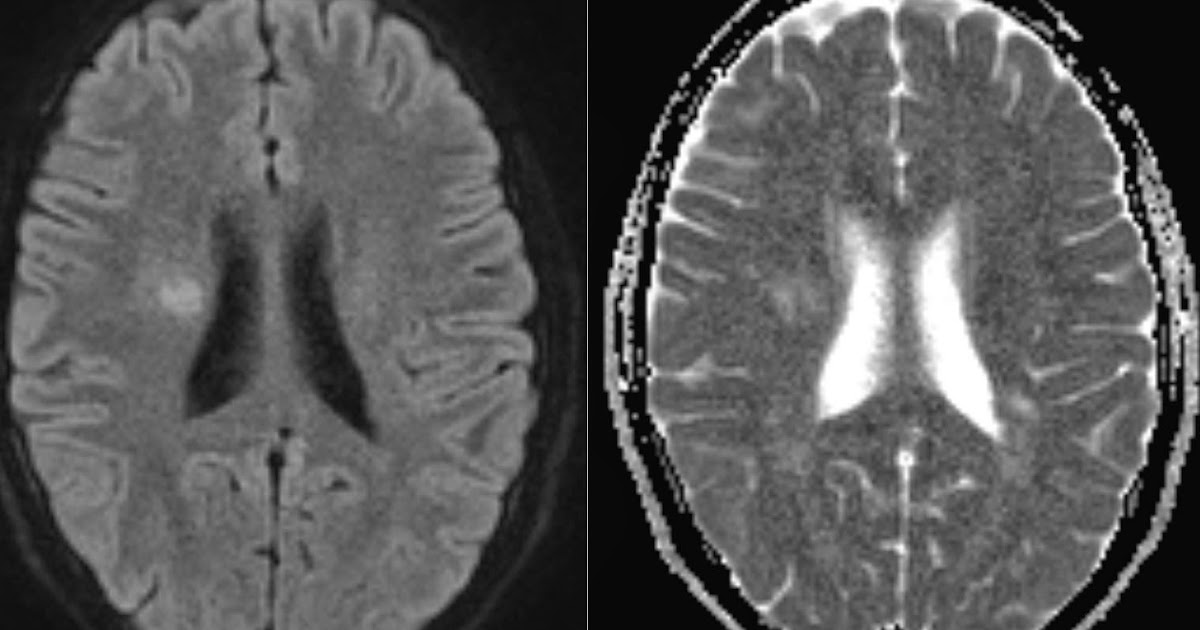

An active MS plaque in occipital lobe with four MRI pulse sequence A

Active MS plaques on DWI Can Ms Plaques Disappear Not all brain lesions are necessarily due to ms, but. If you have multiple sclerosis (ms), odds are that lesions (abnormal areas or changes such as plaques or scarring caused by disease or injury in a tissue or organ) will. Doctors use the presence and location of lesions to help. In ms, chronic inflammation damages these myelin sheaths, which can. Can Ms Plaques Disappear.